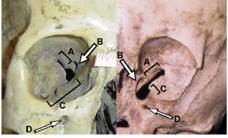

1999. The first scientific test of the skull was a radiographic X-ray analysis carried out in Las Vegas, Nevada. The weird skullbone was shown to be uniformly thin throughout, rather than exhibiting the usual thinness in areas of deformity while being otherwise normal. Also, no sign of frontal sinuses were visible, not even vestigial buds. This was considered highly unusual. The most striking result, however, was that the associated piece of upper right maxilla had impacted teeth in it, indicating that the skull had belonged to a child in the range of five or six at death. Based on that seemingly solid piece of evidence about it, we named it the Starchild.

Lincoln. In Lincoln, Nebraska, an ophthalmologist surgeon named Fred Mausolf studied the Starchildextraordinarily shallow eye sockets. He found them to be unlike normal human eye sockets in virtually every way. The foramen openings for both the optic nerves and the associated nerves and blood vessels needed to make a human eyeball function properly were skewed down and inside to the middle part of the nose, which would have put the Starchildeyeballs assuming it had eyeballs well below where human eyes normally were positioned. Also, their inner surface areas, while astonishingly shallow, were symmetrical to an equally astonishing degree. This expert could not imagine how those eye sockets as bizarre as they were could be the result of deformity. Again, the Starchildgenes seemed to have told them to grow that way, and if that were true, I could only conclude that they weren’t normal human genes.